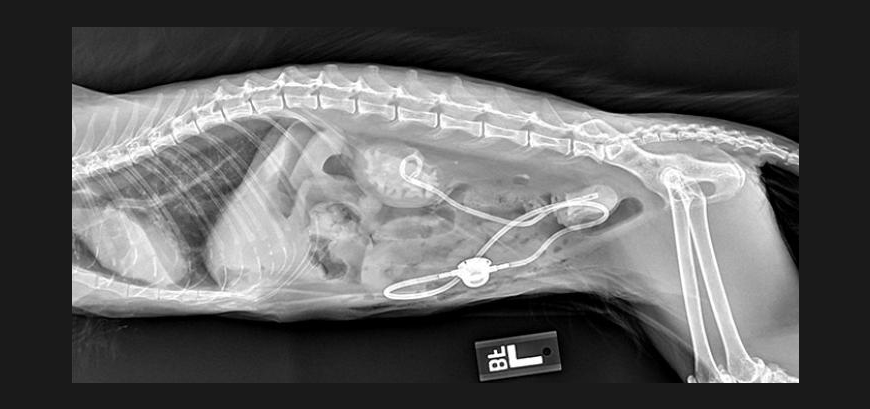

Radiology (X-ray) is a non-invasive diagnostic tool used to assist in the diagnosis of many concerning conditions and traumas.

Additional Radiology Services

• OFA Hips and Elbows